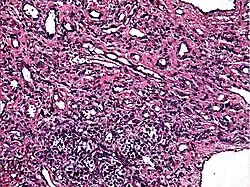

Guz Dąbskiej (łac. angioendothelioma papillare endovasculare malignum, ang. Dabska tumor, malignant endovascular papillary angioendothelioma) – rzadki nowotwór tkanek miękkich o małym potencjale złośliwości, spotykany głównie u dzieci. Guz lokalizuje się zazwyczaj na kończynach, rzadziej w obrębie głowy albo szyi lub w innych lokalizacjach (np. jądro[1]); może przyjmować postać ograniczoną do skóry albo rozlaną, zajmując też tkankę podskórną. W obrazie histologicznym stwierdza się przestrzenie naczyniowe z brodawkowymi tworami i naciekiem limfocytów w podścielisku[2]. Leczenie polega na chirurgicznej resekcji z szerokim marginesem zdrowych tkanek. Nazwa guza honoruje polską patomorfolog Marię Dąbską, która opisała pierwszy przypadek tego nowotworu w 1969 roku[3].